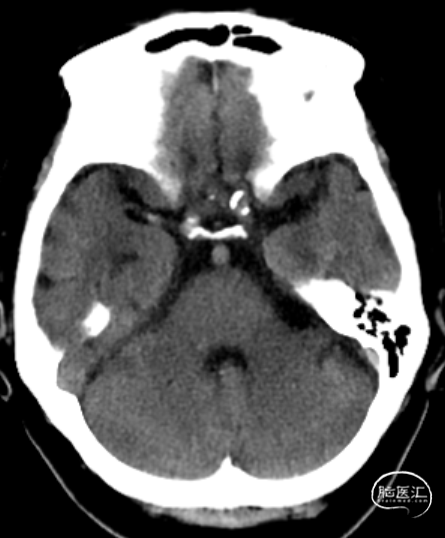

术前影像学检查

脑CTA:左侧颈内动脉闭塞

DSA评估:右侧颈内动脉末端闭塞,颈内动脉走行迂曲

DSA评估:前交通开放,左侧颈内动脉通过前交通动脉向右侧大脑前动脉代偿供血,并逆向充盈至右侧大脑前动脉A1段

DSA评估:后循环未见明显向右侧颈内动脉供血区代偿供血

DSA提示右侧颈内动脉末端闭塞,局部可见“杯口”征;左侧颈内动脉通过前交通代偿,并逆向充盈至右侧A1段;该患者为颈内动脉末端“T”型闭塞。结合房颤病史,病因分型为心源性栓塞。